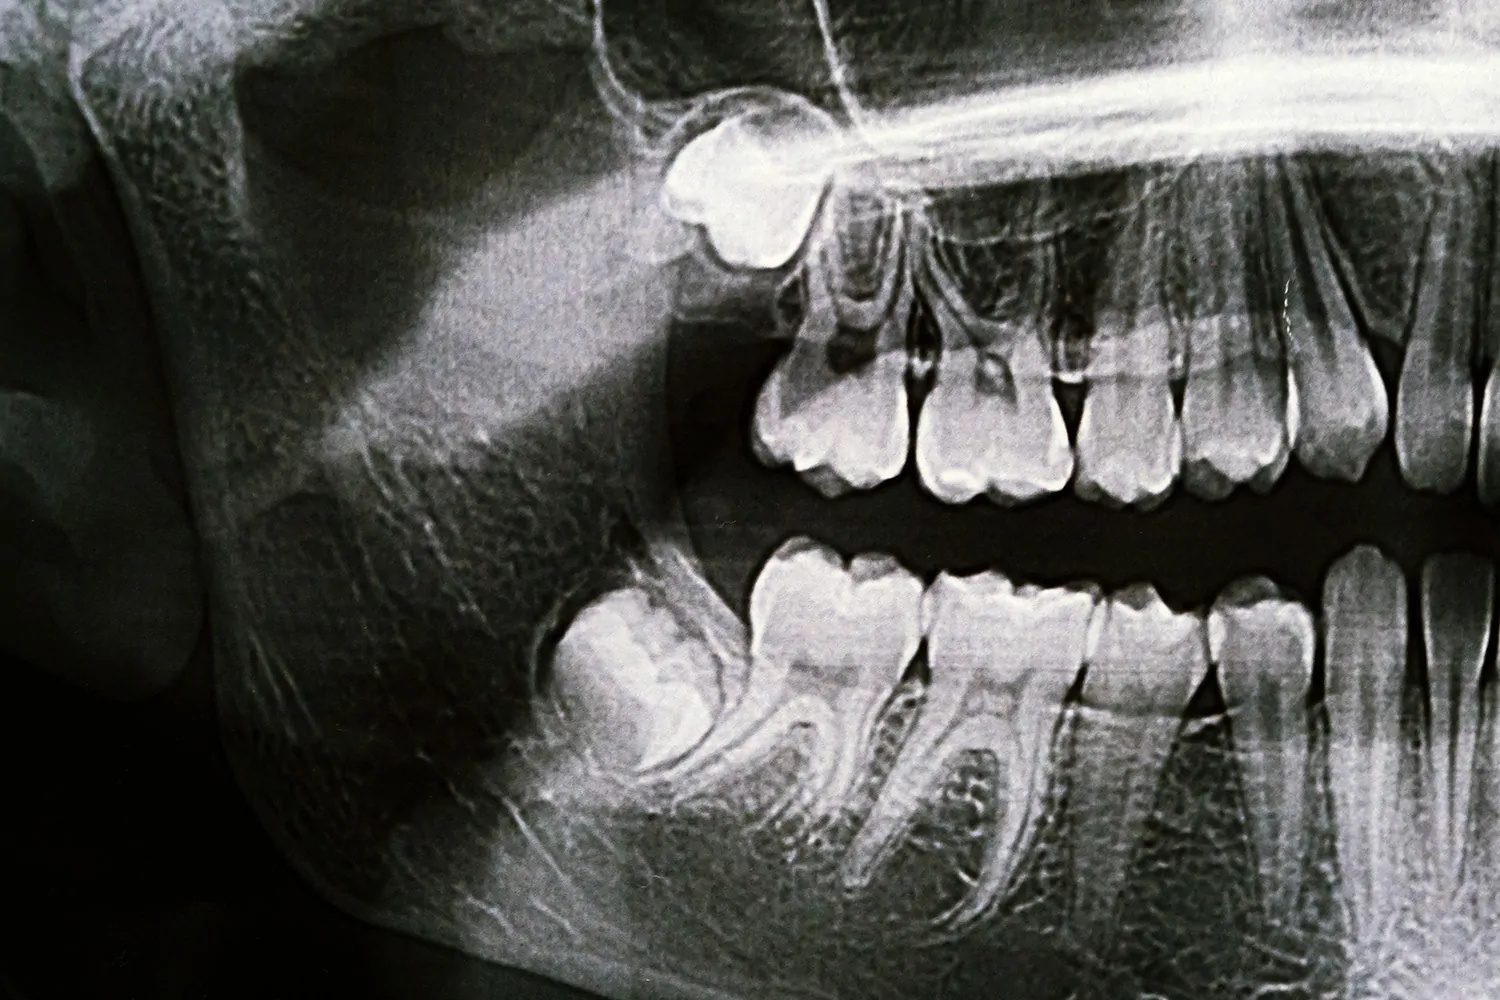

Wisdom teeth are the last molars to develop, typically appearing in late teens or early twenties. Many people lack sufficient space for wisdom teeth, causing them to become impacted. Impacted wisdom teeth can cause pain, infection, cysts, damage to adjacent teeth, and crowding.

We often recommend removing wisdom teeth before problems develop. Younger patients typically have easier recoveries because tooth roots haven’t fully formed and bone is less dense.

During wisdom teeth removal Charlotte procedures, we numb the area or provide sedation. We access the teeth through the gum tissue and bone if needed. Some teeth can be removed whole, while others need to be sectioned into smaller pieces for easier removal.